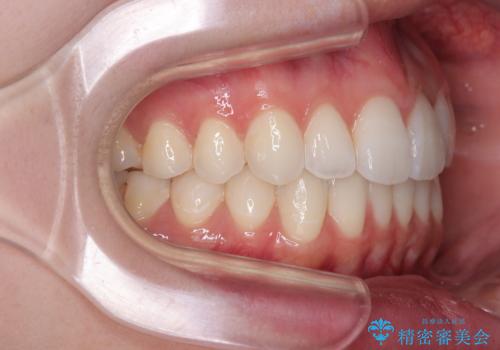

上下前歯の突出感とデコボコを気にして来院された患者様です。

インビザラインによる上下歯列の側方拡大と後方移動、必要に応じてIPR(歯と歯の間を削る)によりスペースの獲得により歯列を整えることとしました。

治療途中、出産や転居があり、2年ほど治療期間が長くなってしまいましたが、前歯の歯並びや飛び出した感覚を無事に改善させることができました。